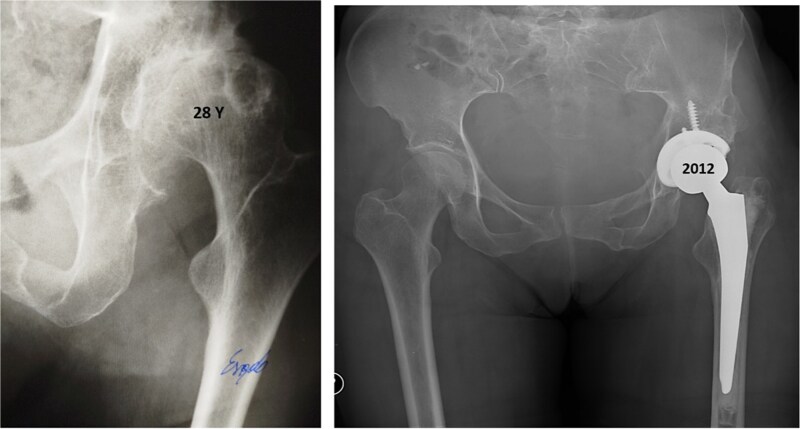

一位35岁的女性髋臼发育不良患者接受了Pol Le Cœur三重骨盆截骨术(TPO)。28年后,她出现疼痛的终末期髋关节骨关节炎,并接受了全髋关节置换术(THA)。植入加压式无骨水泥髋臼杯和骨水泥直股柄,无并发症。在13年的随访中,髋关节x线片显示没有假体不稳定和假体松动的迹象。TPO可能不能完全预防髋关节骨关节炎的进展。本例患者在截骨术后28年出现进行性终末期骨关节炎,需要THA。Pol Le Cœur对于患有低度骨关节炎的年轻成人,TPO是一种治疗症状性髋臼发育不良的可行选择,可有效延缓髋关节假体植入。TPO后混合THA在中期随访中能获得非常满意的临床和影像学结果。

A 35-year-old female patient with acetabular dysplasia underwent a Pol Le Cœur triple pelvic osteotomy (TPO). Twenty-eight years later, she presented with painful end-stage hip osteoarthritis and underwent total hip arthroplasty (THA). A press-fit cementless acetabular cup and a cemented straight femoral stem were implanted without complications. At 13-year follow-up, hip radiographs revealed no signs of prothesis instability and no signs of implant loosening. TPO may not completely prevent the progression of hip osteoarthritis. In this case, the patient developed progressive end-stage osteoarthritis 28 years after the osteotomy, requiring THA. Pol Le Cœur TPO is a viable treatment option for symptomatic acetabular dysplasia in younger adults with low-grade osteoarthritis, effectively delaying hip prosthesis implantation. Hybrid THA after TPO can yield very satisfactory clinical and radiographic outcomes at mid-term follow-up.